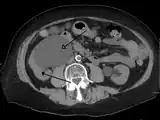

- Urine jets[16]